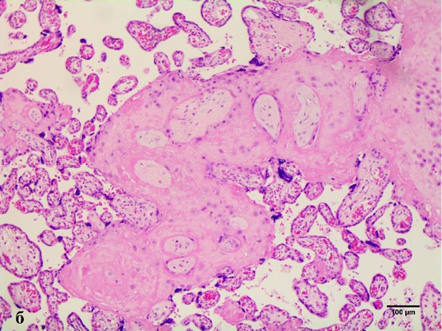

Assessment of histological features of the placenta in 3 of 32 samples (9.4%) revealed high-grade fetal vascular malperfusion at various stages of development. Stem vessels of 2–4 orders were diagnosed with thrombus in initial recanalization and partial fibrinoid organization. The surrounding villi were vascularized, immature with hyalinized syncytiotrophoblast and completely absent trophoblast with varying degrees of intravillous stromal fibrosis (Fig. 4a) due to prolonged ischemia. In 13 samples (40.6%) of the placentas studied, the obliteration of the 2nd and 3rd order spiral arteries in the anchoring villi was found (Fig. 4 b).